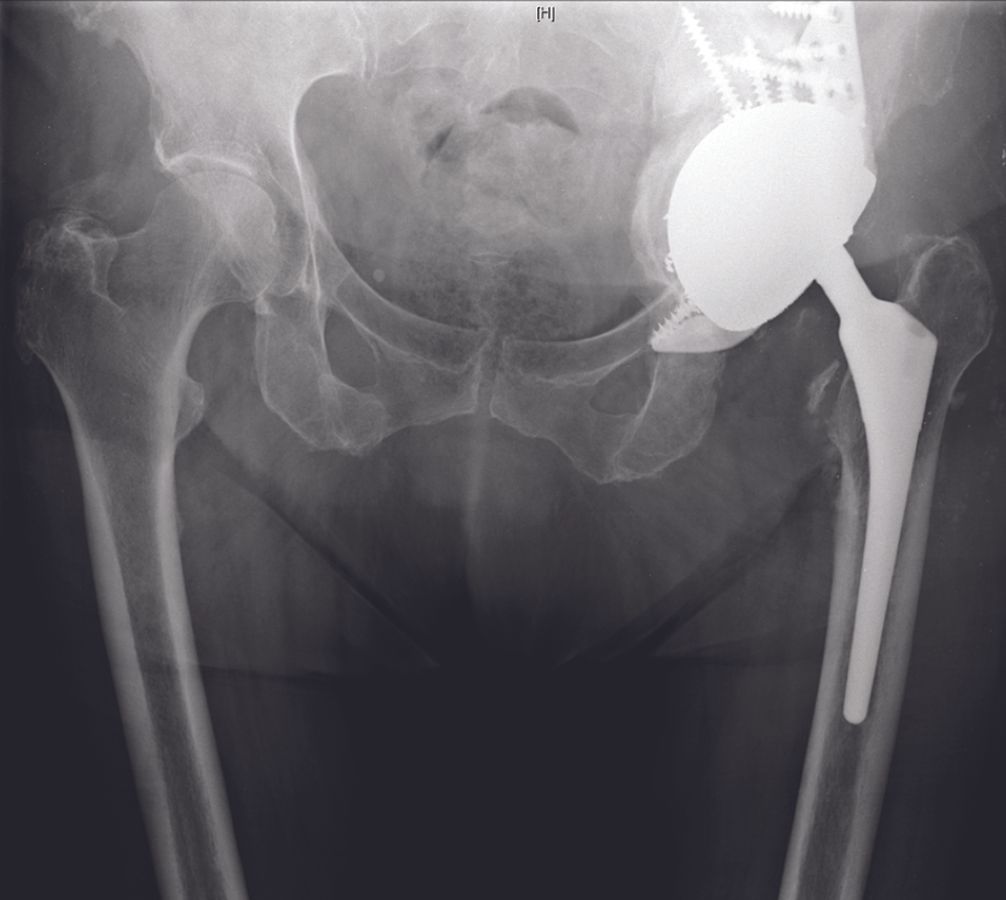

Finally, a polyethylene liner is cemented into the cup-cage construct with an appropriate degree of inclination (40°) and anteversion (15°) independent of the position of the cage. In cases with severe abductor deficiency, a dual-mobility cup is utilized to prevent dislocation (Fig. 12).

During cementation, the cement bonds to all components of the cup-cage construct to eliminate micromotions between the individual components. Finally, a trial reduction is done to confirm leg length, horizontal offset, stability and range of movement (Figs. 13 and 14).